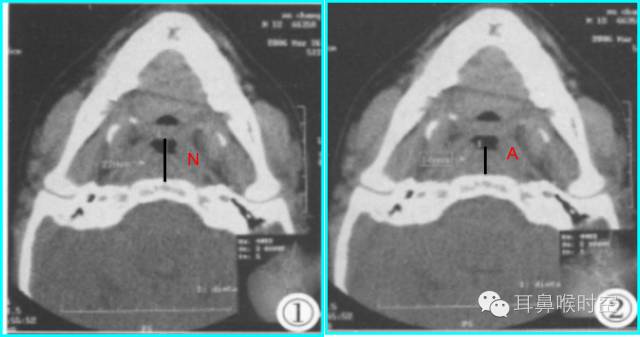

根据经典Fujioka 等 X 线平片测量法原理:

A/ N 比:测量腺样体最大厚度与自硬腭上缘到颅底蝶枕骨的软骨结合部的距离之比

PAS:后气道间隙(pharyngealairway space , PAS)的宽度(软腭表面与腺样体表面之间有效气道宽度)。

采用SE 序列矢状面T1WI

选择正中矢状面,分别测量两条径线(图1、2)

N 线:即从蝶骨体2枕骨斜坡的软骨结合部后缘(O点)至硬腭与软腭上缘交界处的连线N

A 线:过O点沿枕骨斜坡下缘作延长线L,取腺样体下缘最凸点作L线的垂直线。

A/N比:分别测A、N值,计算A/N 比